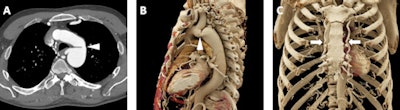

Furthermore, it also provides highly detailed visualization of pulmonary arterial vascular conditions that may require surgical intervention such as pulmonary artery aneurysms.

A 52-year-old woman with a history of pulmonary artery aneurysm of unknown etiology. A: Axial postcontrast 2D CT image demonstrates marked enlargement of the main pulmonary artery (measuring 5.2 cm, white arrowheads). B: Volume-rendered image also demonstrates the dilated main pulmonary artery (white arrowheads), with improved visualization of the relationship of the aneurysmal vessel relative to other vascular structures such as the aortic arch and the branching pulmonary vessels. C: Cinematic-rendered visualization once more shows the aneurysmal main pulmonary artery (white arrowheads) and its 3D relationship to other major vessels. The photorealistic detail and shadowing available with cinematic rendering creates high contrast that better highlights the smaller pulmonary vessels that overlie the main pulmonary artery in this view (white arrow).The method's photorealistic shadowing effects provide accurate spatial information about small vessels within the complex branching pattern of the pulmonary vasculature near the pathologic structure.